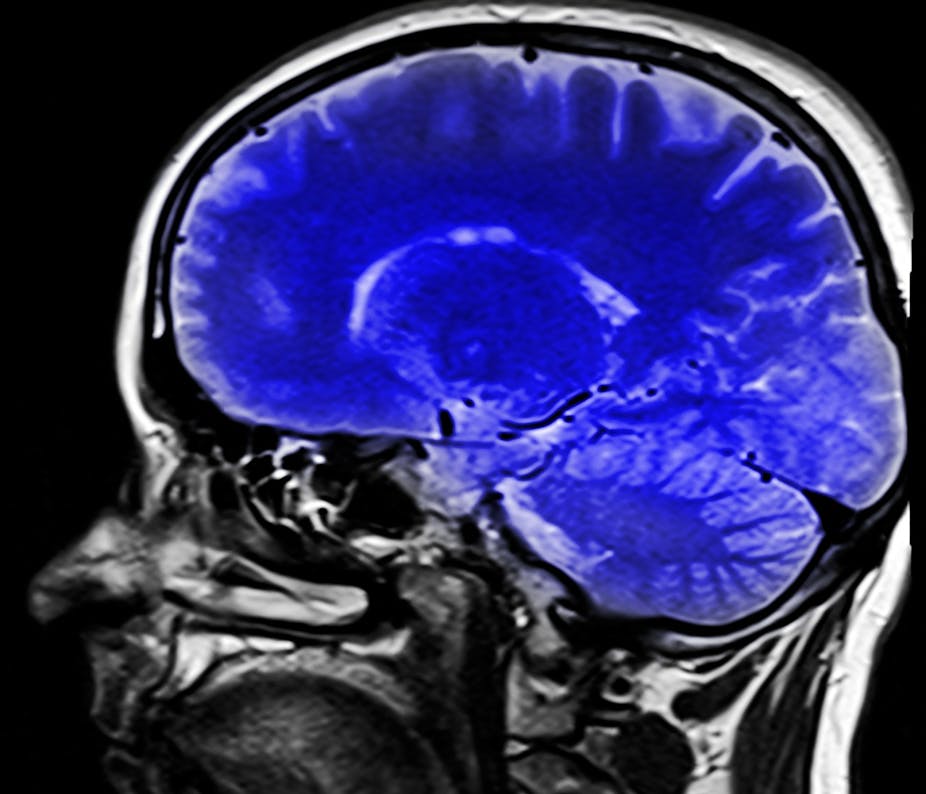

Studies of the brains of healthy people during cognitive training of working memory have shown both changes in brain activation and also in dopamine receptors. Brain scanning techniques such as fMRI and PET, which can image the neural network involved in forms of cognition and study receptors important for drug actions, are already helping us understand the damaged brain and possible treatment effects. Furthermore, developments in real time fMRI feedback as a treatment for neuropsychiatric disorders, such as anxiety and depression, will be key to training top-down cognitive control over the emotional brain.

One of the most important objectives of the Human Brain Project is to make it easier for neuroscientists to organise and access the massive volumes of heterogeneous data, knowledge and tools produced by the international neuroscience community. So-called connectomics, the study and production of connectomes – neural maps of the brain – will combine a number of techniques for mapping and studying connectivity within the brain. Understanding these connections could revolutionise our understanding of how the brain functions and the areas affected in “connectopathies” where there is abnormality in the connections in brain networks, including disorders such as autism, schizophrenia and Alzheimer’s disease